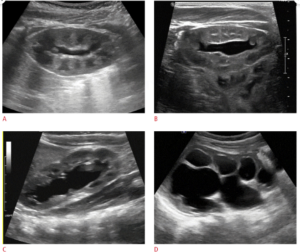

Siêu âm là kỹ thuật chẩn đoán hình ảnh quan trọng trong chẩn đoán và theo dõi. Siêu âm xác định có giãn đài bể thận, mức độ giãn, niệu quản không giãn. Trên siêu âm cần thiết đo các kích thước của thận, đường kính trước sau bể thận và bề dày chủ mô thận. Các thông số này rất quan trọng trong quá trình theo dõi trước và sau điều trị. Siêu âm có thể phát hiện hội chứng hẹp khúc nối do cầu mạch máu.